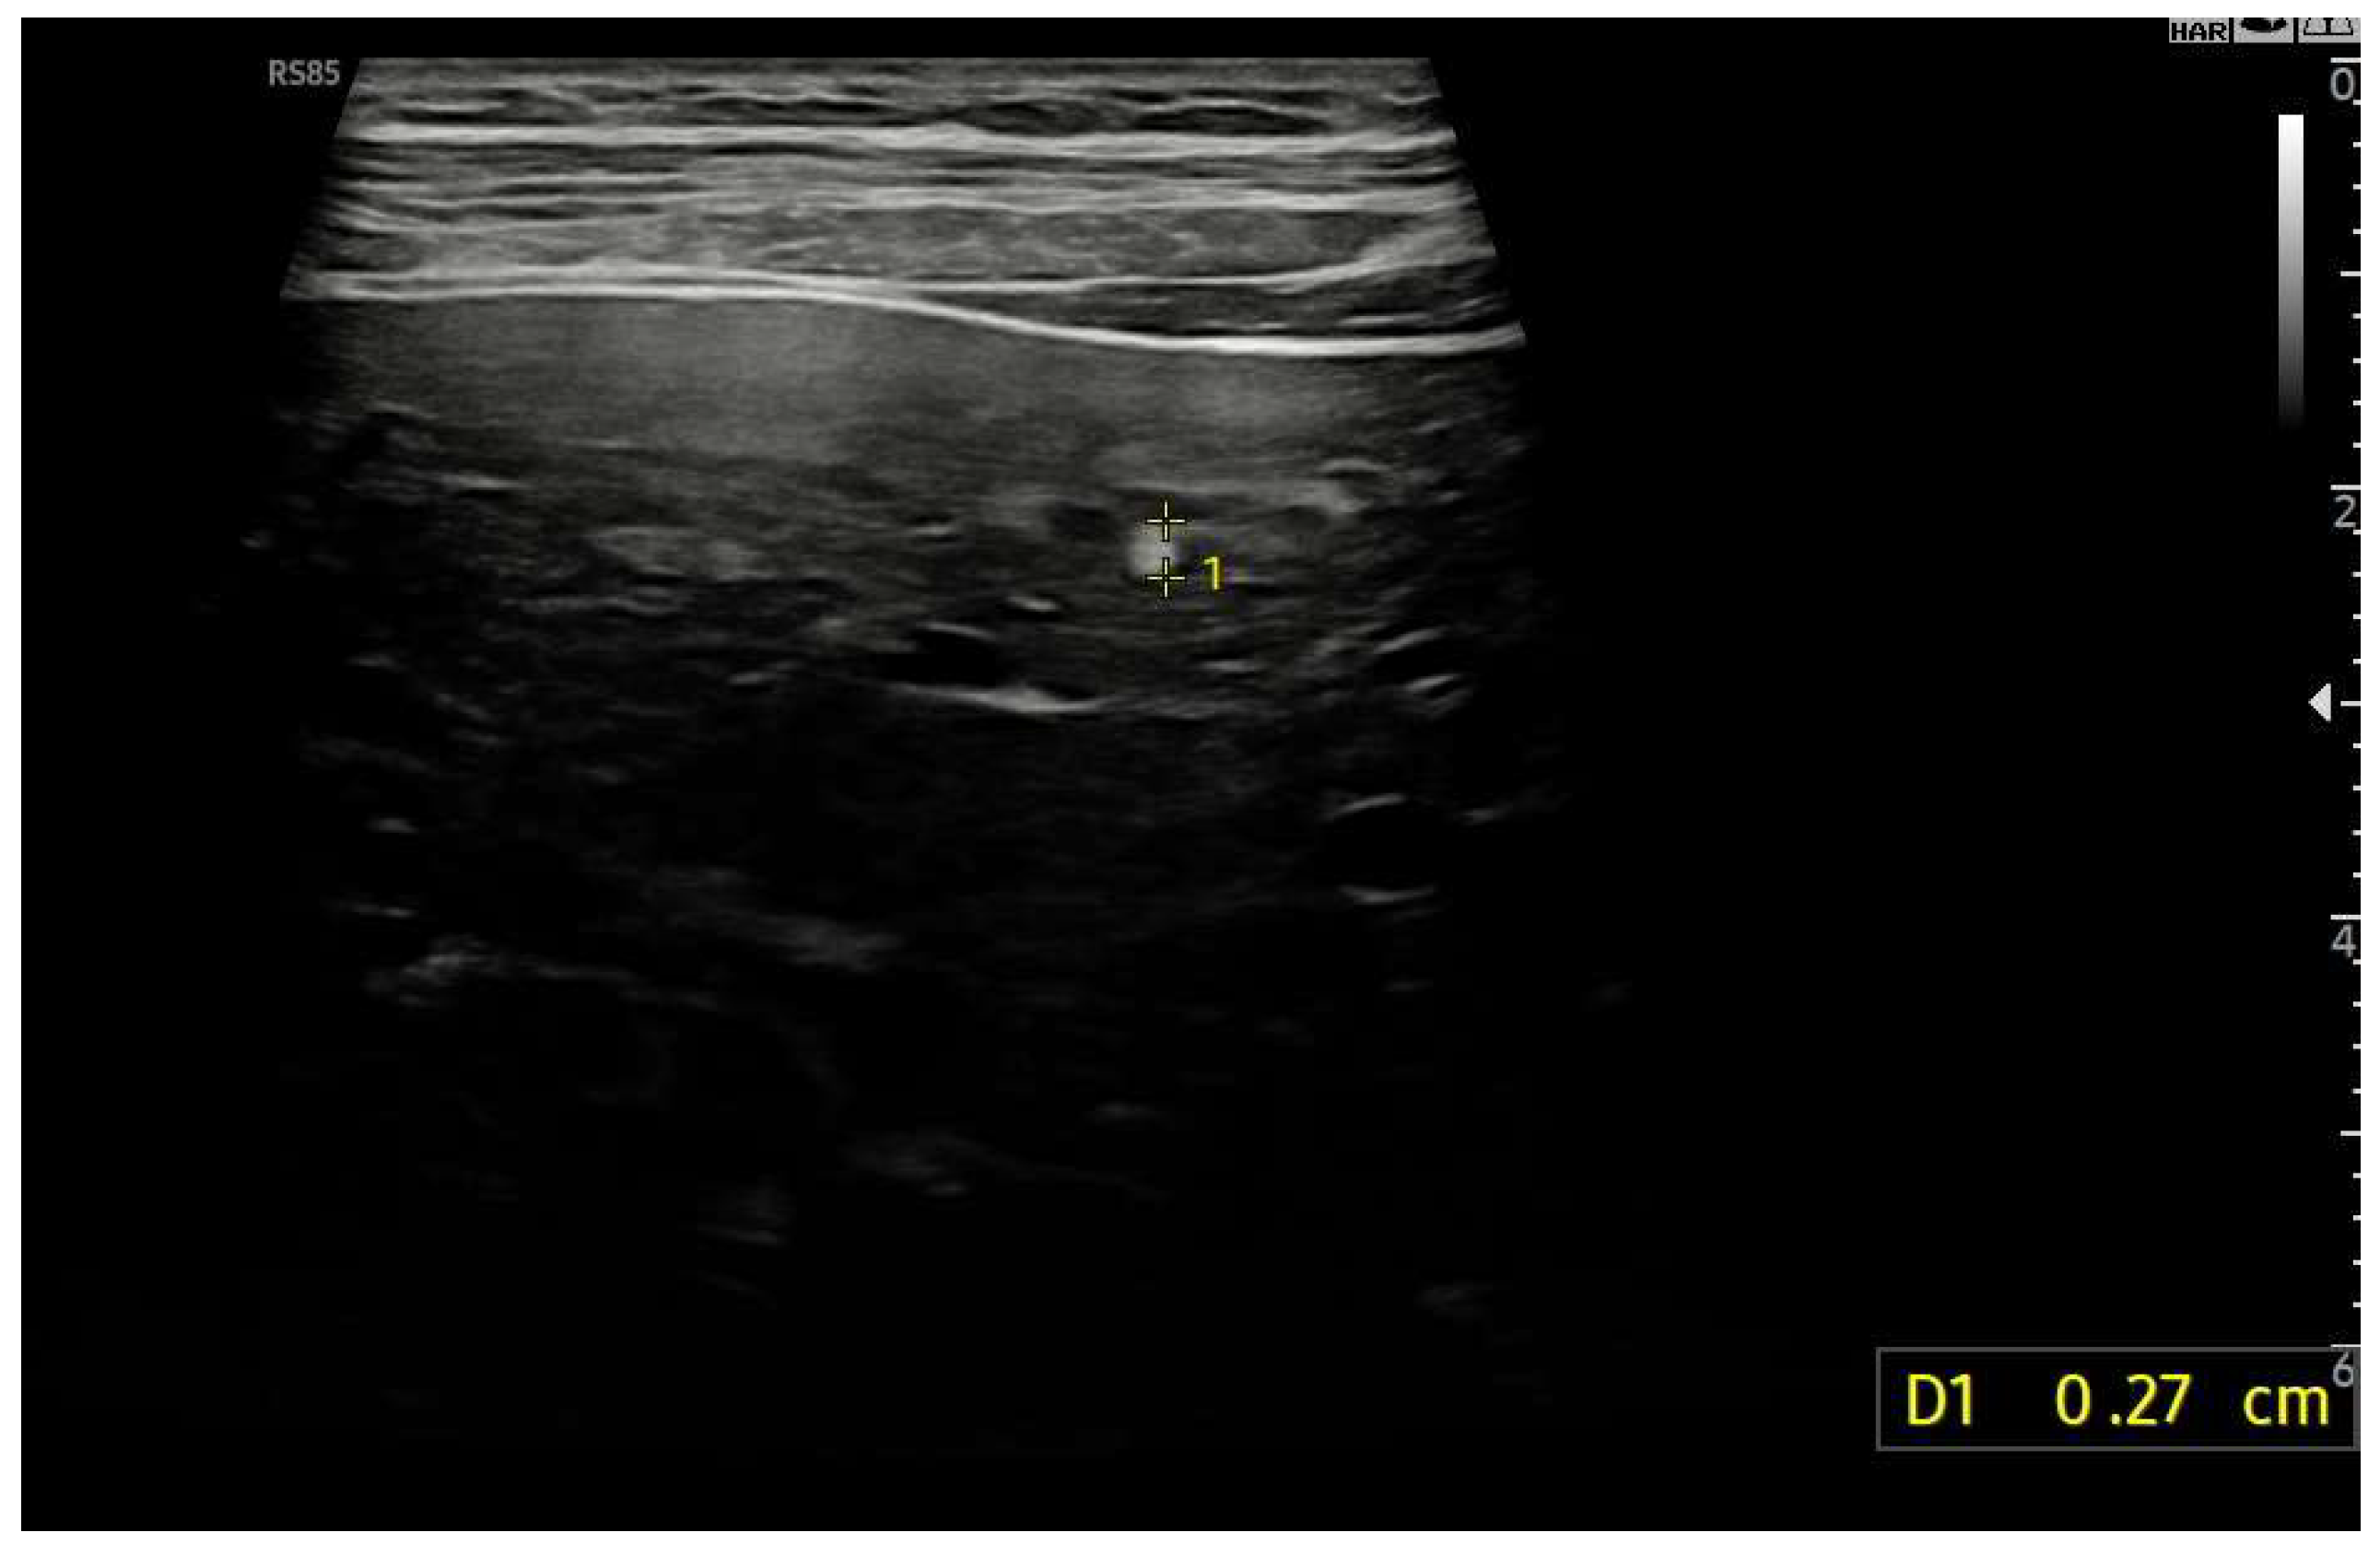

Figure 17.

Hyperechoic oval lesion of 2.7 mm, compatible with a FNH-like nodule, identified using a high-frequency linear probe.